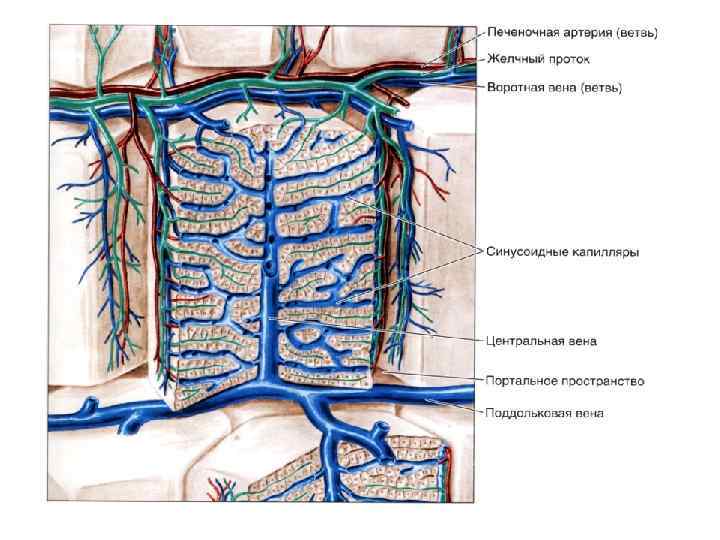

ПЕЧЕНЬ ЧЕЛОВЕКА

CV- центральная вена BD- желчные протоки * - синусоидные капилляры

1 - внутридольковый синусоидный капилляр, 2 - эндотеиальная клетка, 3 - поры в эндотелии, 4 - звездчатый макрофаг, 5 - перисинусоидальное пространство Диссе, 6 - ретикулярные волокна, 7 - микроворсинки гепатоцитов, 8 - гепатоциты, 9 - желчный капилляр, 10 - перисинусоидальный липоциты (клетки Ито), 11 - жировые включения, 12 - эритроциты

Желчный капилляр Плотный контакт Десмосома Звездчатый макрофаг (Купферовская клетка) Эндотелиоцит Перисинусоидальное пространство Диссе Ретикулярное волокно Липоцит Ямочная клетка Плотный контакт Ретикулярное волокно

1 - зона оптимального кровоснабжения, 2 - зона умеренного кровоснабжения, 3 - зона наихудшего кровоснабжения (наиболее уязвима при интоксикациях)

Триада печени

Триада печени

Центральная вена и синусоидные капилляры